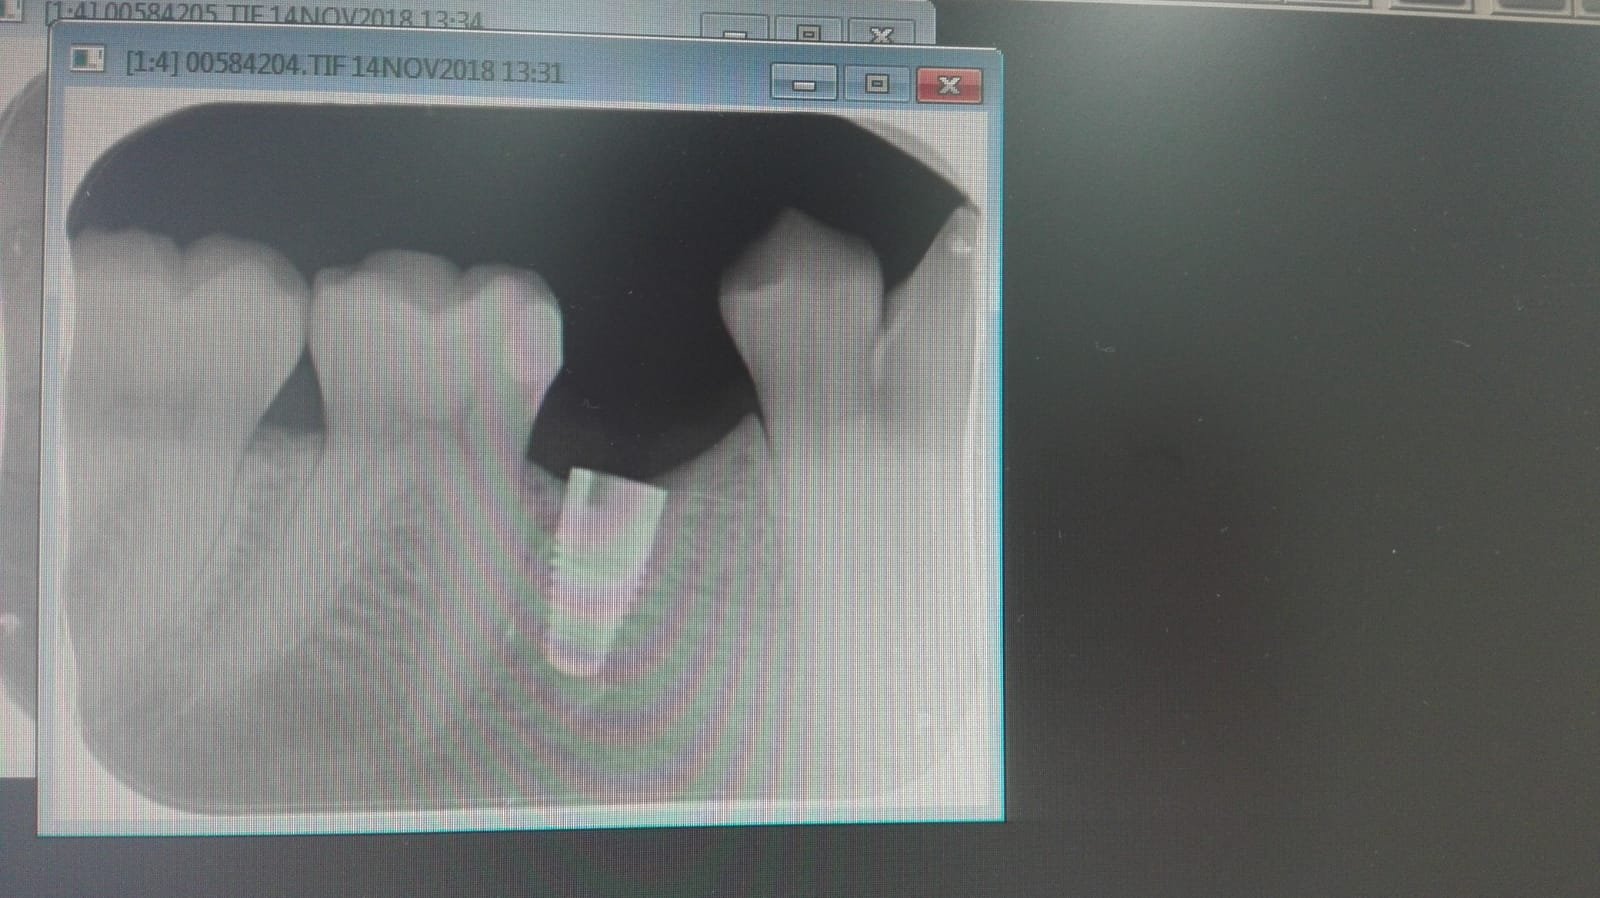

Buenos días, necesitaría saber que implate es este. Se lo han puesto hace unos meses en la Universidad Complutense y no sabe ni marca, conexión, plataforma,etc ¡gracias!